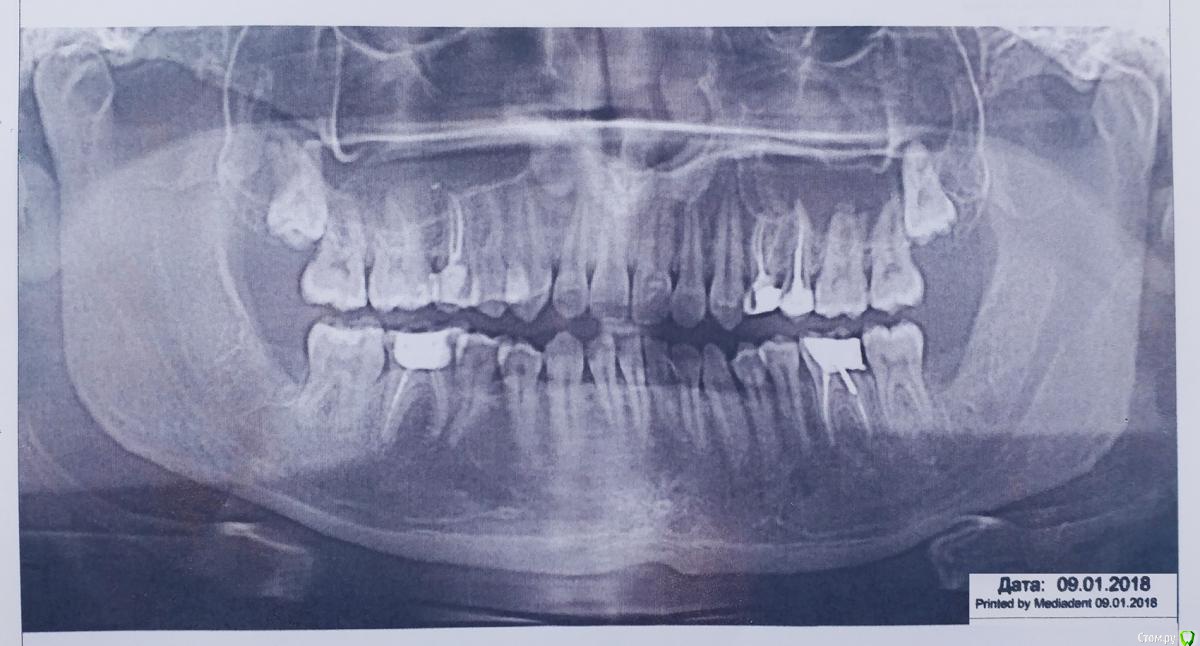

post-54820-0-18771900-1523282090_thumb.jpg  (снимок сделан в январе, спустя 3 мес после удаления)

Во время осмотров и снятия дренажа упомянул врачу. Тот предположил что раз 8рки сильно давили, то с их исчезновением стало больше свободы и зубной ряд чуточку разошелся.

Когда болевые ощущения от самой раны прошли — стало ясно что трудно сомкнуть челюсти , зубы будто не соединяются должным образом. Ночью всегда спал с закрытым ртом, теперь же приходится слегка приоткрывать.